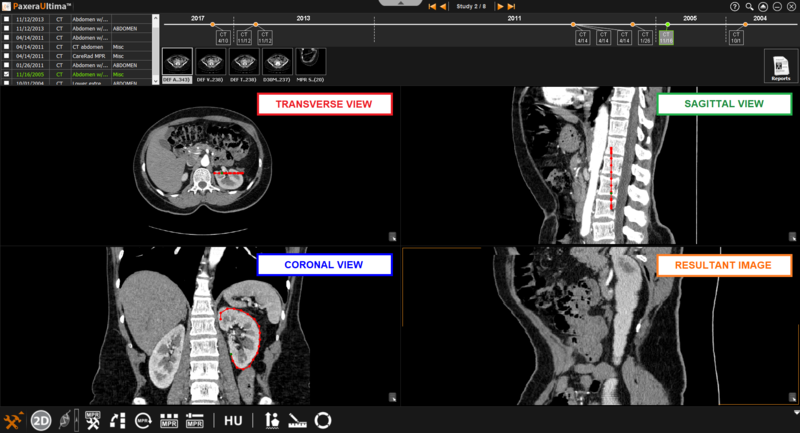

9.4.5. Curved Mode

The curved mode allows the user to click on a number of points in order to create their own curved line.

» Create curve- simple click on the starting position of interest and then continue to click along the path of interest. A continuous line will be created between each clicked point and a circle will be shown for each click that was conducted. To finish the curve, simple double click using the mouse.

» Adjust curve– To adjust the shape of the curve, simple select one of the points shown along the curve and drag it to the new position of interest

» Panorama mode- creates resultant image taking all views into account when curve is drawn (panorama mode is only accessible in the curved MPR mode).

If this option is unchecked, any adjustments made in a different window from the original curve will change the view of the resultant image.